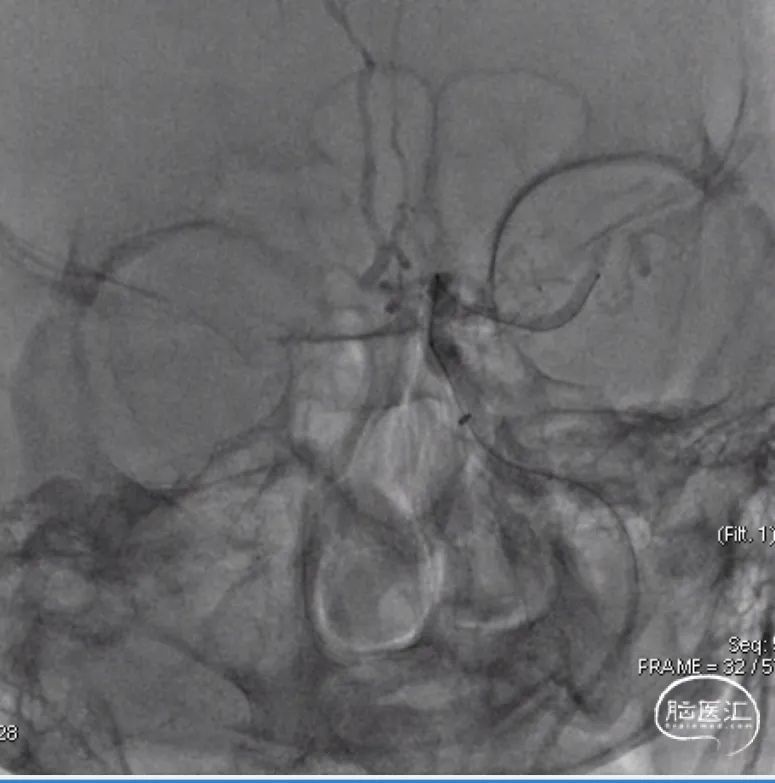

支架释放:

4mm*25mm NeuroHawk取栓支架释放,支架显影良好,支撑性较好。

术后造影:

取栓一次,可见一枚小血栓取出,即刻造影显示mTICI 3级再通。